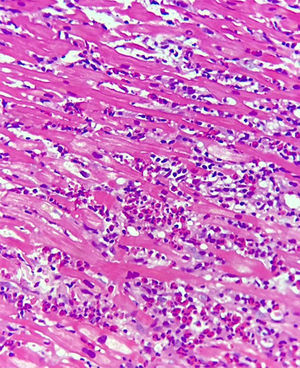

Ingresa a nuestra institución en muy malas condiciones, en choque cardiogénico refractario por lo cual se consideró candidato a soporte venoarterial con ECMO, con adecuada tolerancia y respuesta. Paraclínicos de ingreso a nuestra institución: Eco TT: ventrículo izquierdo de diámetro normal, deterioro difuso de la contractilidad, paredes gruesas. FE del 20%, BNP: 1430, HB: 10,8, HTO: 30,2, LEU: 11,3, NEU: 78%, EOS: 1,8% (tabla 1). Se le realiza biopsia endomiocárdica, la cual reporta miocarditis eosinofílica sin fibrosis según criterios de Dallas (figs. 1 y 2). Reporte de anticuerpos, strout y biopsia negativos para Chagas. Teniendo en cuenta adecuada tolerancia, mejoría de las condiciones hemodinámicas y recuperación de la función sistólica del ventrículo izquierdo se decidió retiro de ECMO al tercer día lográndose destete exitoso. Se realizó ECO TT de control con mejoría de la FE (30%), respecto al ingreso, BNP de control de 41. Se realizó retiro de infusiones de soporte con adecuada tolerancia, sin signos de bajo gasto, asintomático cardiovascular, gasto urinario adecuado. Previo al egreso se decide realizar nuevo ECO TT de control al día 10 con evidente recuperación de la función ventricular FE 55% (tabla 2). Teniendo en cuenta la adecuada evolución clínica del paciente, con recuperación de la función ventricular y adecuada tolerancia a la medicación se considera dar egreso al paciente.

Servicio Patología Fundación Cardiovascular de Colombia.